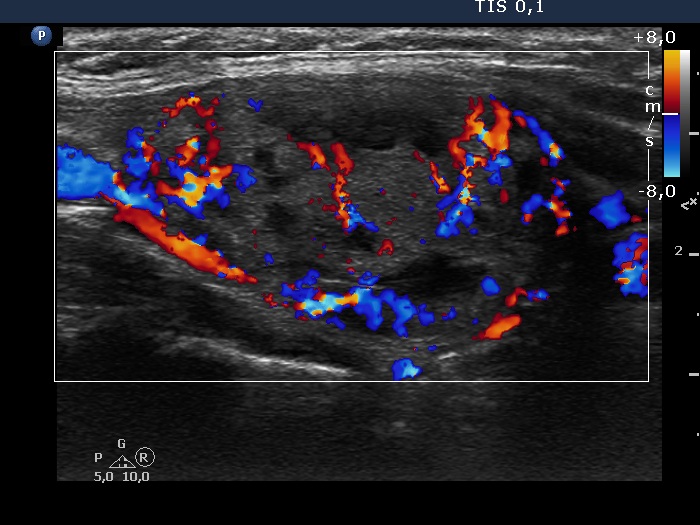

Study on 100 consecutive patients with thyroid nodule - case 051 (ultrasonographic picture 5)

Right lobe, longitudinal view, color Doppler mode. This is a combined perinodular and intranodular vascularity. The latter is significantly increased.